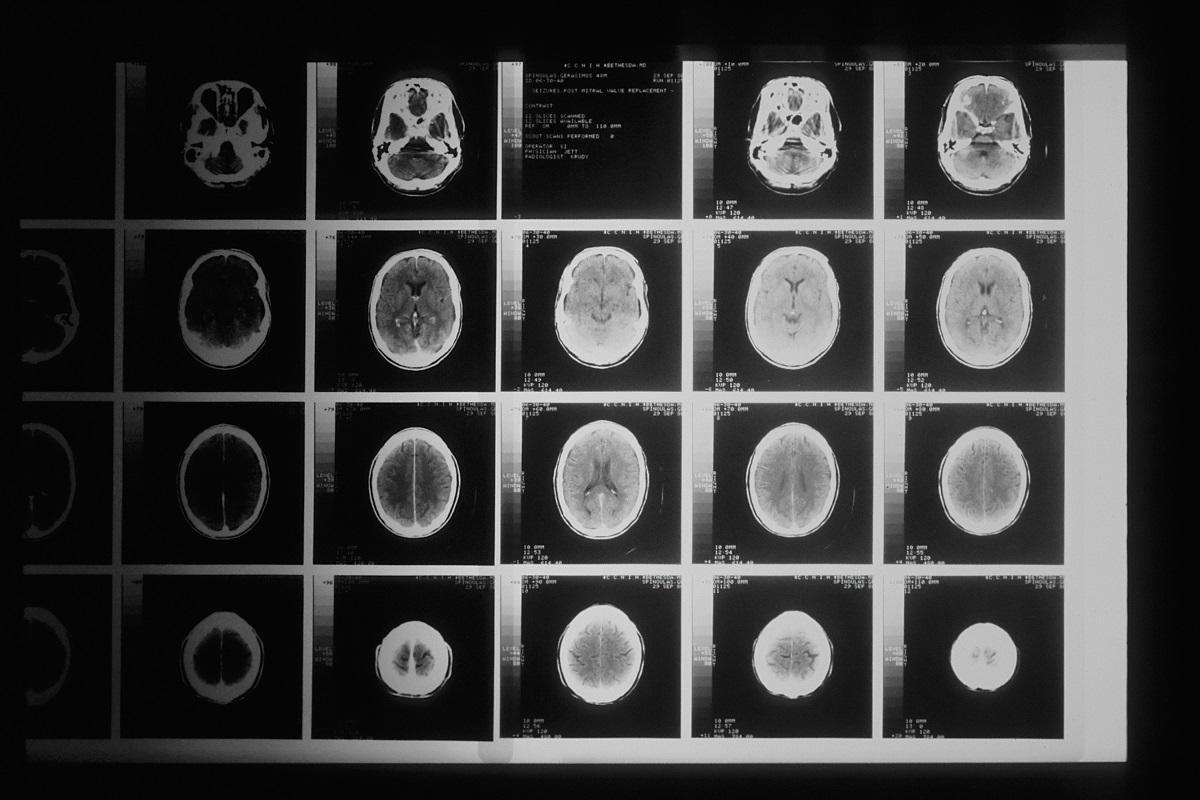

IRM de plusieurs cerveaux